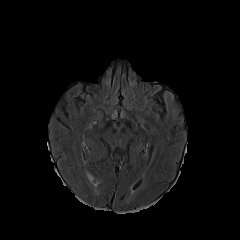

MRI